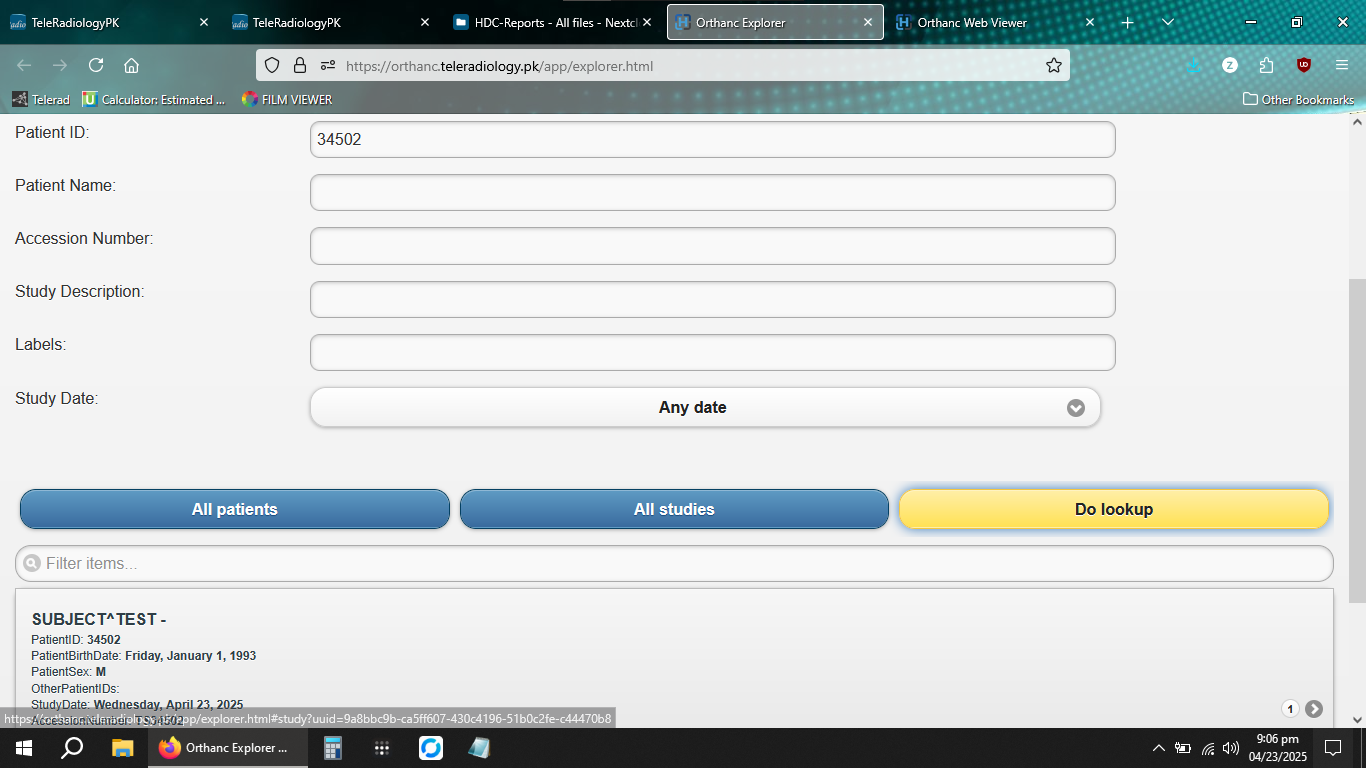

We provide guidance for implementation of our PACS server into respective Radiology modalities including MRI, CT, X-Rays and Ultrasound. For machines without activated DICOM nodes, studies can be sent to us via dedicated password protected links after retrieval from the machines.